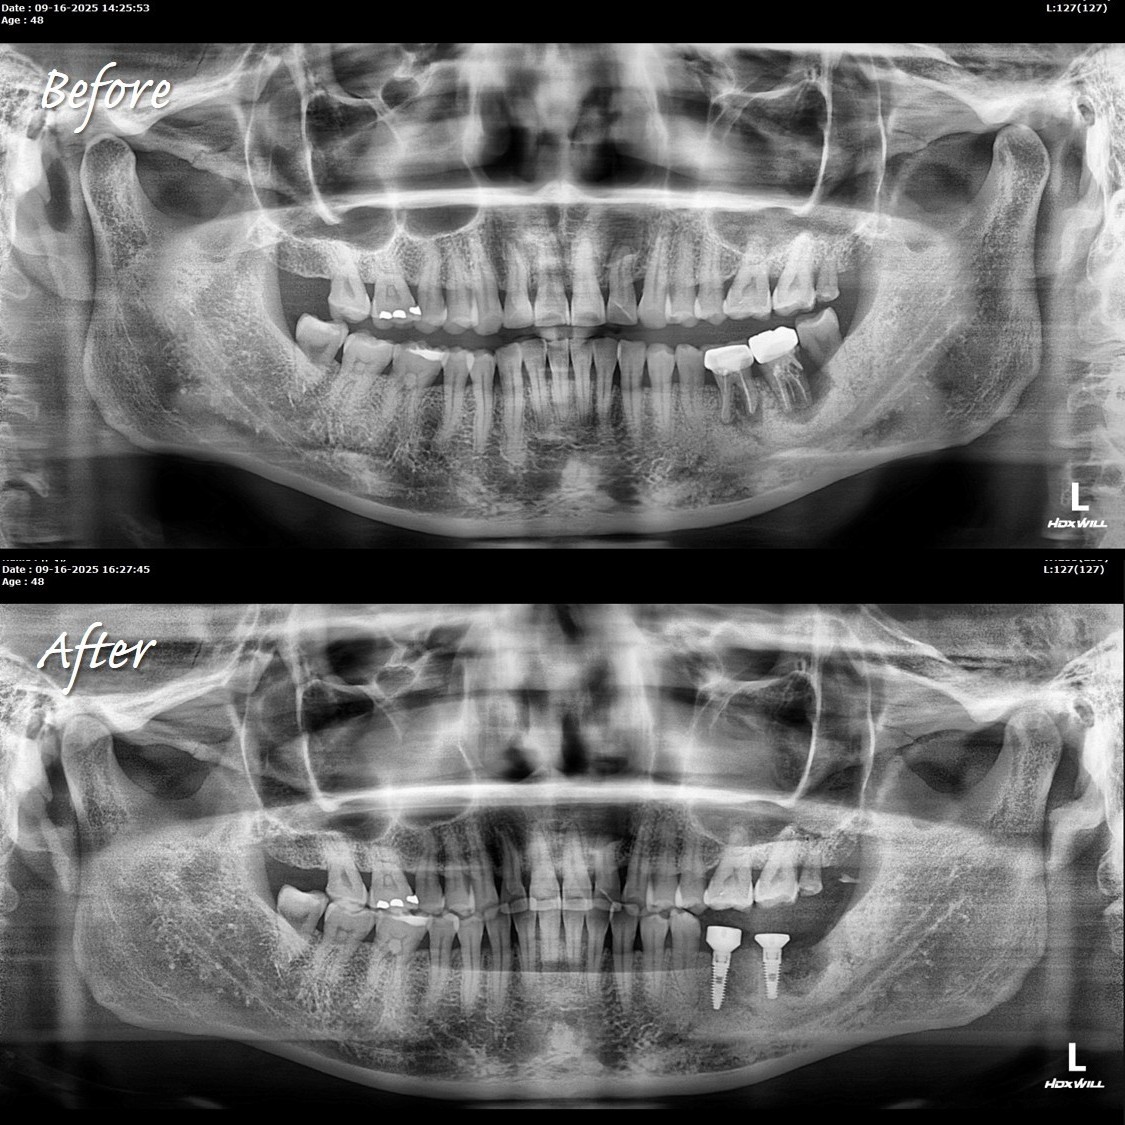

陳俊龍博士分享,診所傳來X光片,讓他疑惑自己沒上班,怎麼會有植牙案例。

仔細一看才知道,原來是年輕醫師完成的植牙案例,成果相當漂亮,堪稱完美的植牙案例。

他也只在陳博士身邊學習一兩年,就能做到比「大師」還厲害的案例。從X光片的時間能看出,同一天下午完成即拔即植。

陳博士強調:工具對了、方法正確,就能做到。眼見為憑,成果就是最好的證明。能在短時間內達到這樣的水準,已經非常不容易。